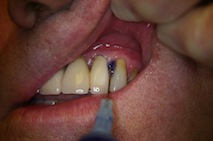

Přístroj na principu světlem aktivovaná desinfekce neboli fotodynamická antimikrobiální chemoterapie. Přístroj s okamžitým účinkem ničí veškeré mikroorganismy bez jakýchkoli vedlejších účinků. Jedná se o bezbolestné ošetření, které nevyžaduje anestezii, nemá vedlejší účinky a ničí 99% bakterií. Používá se především v parodontologii a implantologii při léčbě zánětů v okolí zubů a implantátů (dezinfekce tzv. chobotů), záchovné stomatologii (ošetření kazů) i endodoncii (dezinfekce kanálků zubu).